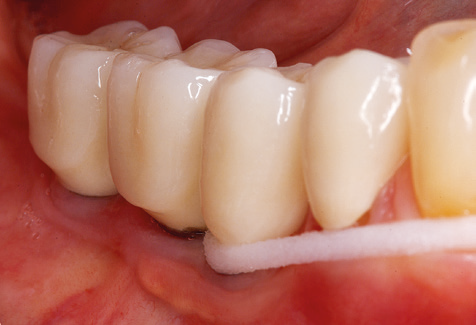

Fig. 9: Le superfici accessibili di impianti e denti sono lucidate con coppette da lucidatura e composti lucidanti adatti. - Fig. 10: Rispettare le istruzioni d'uso di ausili adeguati per l'igiene orale a casa dovrebbe far parte di SPT. - Fig. 11a eb: Situazione clinica 12 anni dopo l'inserimento del restauro protesico. Durante questo periodo, sono state osservate solo la rottura della ceramica del rivestimento estetico sul dente 47 e la necessità di un trattamento endodontico del dente 12. Tutti i restauri funzionano ancora come previsto.

Un'assistenza standardizzata e regolare a misura di rischio nell'ambito di SPT è la chiave per il successo del trattamento clinico a lungo termine nei pazienti con situazione periodontale compromessa. Ciò è particolarmente vero per i pazienti a cui vengono applicati impianti dopo il trattamento parodontale completato con successo (Fig. 11a e b).